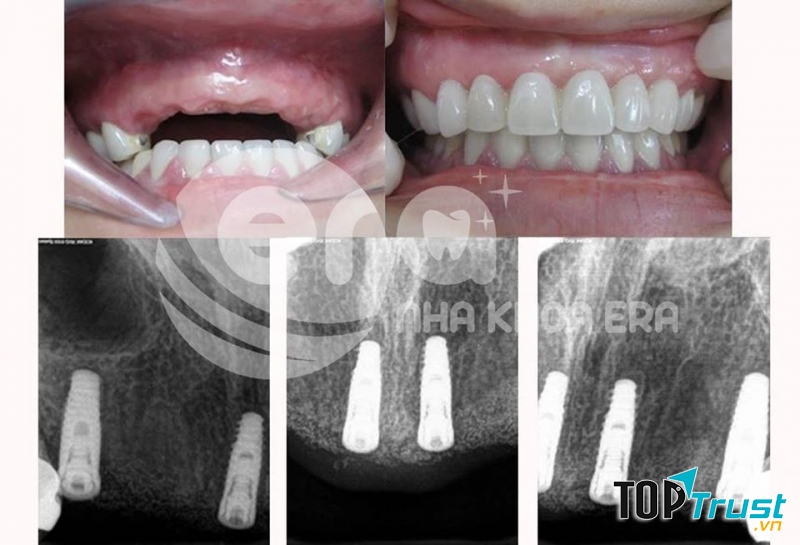

Từ khi thành lập đến nay, ERA Dental đã phục vụ hơn 8445 khách hàng, với 5772 ca chỉnh nha thành công và kiến tạo hơn 2274 nụ cười. ERA rất hạnh phúc vì đã mang lại nụ cười đẹp hơn cho khách hàng và giúp họ trở nên tự tin hơn trong công việc và cuộc sống. “Mang đến giải pháp phù hợp nhất cho khách hàng sao cho cân đối giữa tính thẩm mỹ và yếu tố sức khỏe với chi phí hợp lý nhất” là tất cả những gì mà ERA Dental mong muốn và sẽ mang đến cho mỗi khách hàng của mình.

Bên cạnh đó, ERA Dental đã ứng dụng thành công các công nghệ hiện đại hàng đầu trên thế giới vào các dịch vụ nha khoa như: Chỉnh nha, thiết kế nụ cười DSD, cấy ghép implant, phục hình sứ thẩm mỹ,… và tất cả đều được đích thân các chuyên gia áp dụng theo quy trình chuẩn, tuân thủ nghiêm ngặt các quy định của cơ quan y tế từ khâu thăm khám, tư vấn, chụp phim, đến điều trị.